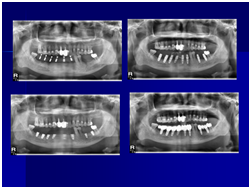

患者的原始片 91/06/13

患者陳先生於91/06/03初診,為一個牙周病患者,合併有右下缺牙。經過保守性牙周處理後,於91/08/14放置右下三顆植體。

完成後大約半年至一年進行一次例行性追蹤檢查,並無特別問題。以下為96/08/13時的追蹤小片,可以見到當時三顆植體的骨高度並無顯著變化。但右下第一小臼齒此時發現有搖動度增加的情形,當時對該顆牙做了咬合調整,降低咬合功能負荷,希望能有所改善。

96/08/13

患者之後於96/11/08在右下第一小臼齒與植體間有膿胞產生,並於97/02/21確認右下第一小臼齒有根裂的情形,因此在97/02/29拔除此牙;經過將近半年後,於97/09/23放置一顆植體於此位置

97/02/21 確定根裂時拍的片子

97/02/21

97/09/18 拔牙半年後安排右下第一小臼齒植牙前

97/09/23 右下第一小臼齒植牙完成時

98/01/08經過三個半月做右下第一小臼齒的二階暴露,發覺鄰牙的植體高度竟已掉下來

980305幫患者補角化牙齦並翻開清除發炎組織,期待能阻止繼續骨破壞

期間患者偶爾出血但並無明顯不適

直到經過一年半後,於99/07/19又有明顯發炎,拍攝追蹤片,發覺連同更遠心的那顆植體的骨頭也破壞下降了

99/07/19

和患者積極溝通,由於患者神經管上的骨高度並不理想,建議積極移除中間兩顆有問題的植體重放,阻止發炎與骨破壞繼續下降;但患者想再追蹤。

患者於99/10期間因起床後有暈倒現象,住院後持續吃抗凝血劑,雖有發炎但不致於不舒服,因此一直不願積極處理;終於在100/03/1將兩顆植體移除,並於100/05/23回診評估再次植牙的條件。

100/05/23

於100/06/07重新放置兩顆植體

並於100/10/25將中間兩顆植體做二階接出

由於前後植體的高低差距太大,決定將中間兩顆高度較為一致的植體假牙做連結,但前後兩顆做單顆假牙的設計。

100/11/21 補綴完成

目前植體周圍的組織都很理想健康並追蹤中。